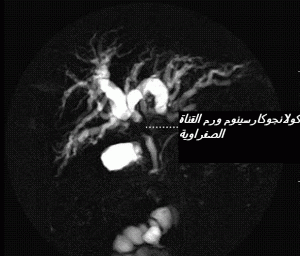

(11) فوق الملتقى الصفراوي الأعلى ( بإضافة وجود أو عدم وجود الحصى في القناة الصفراوية الرئيسية و / أو المرارة ). يتعلق الأمر بمرض نادر حيث تم وصف صنفه العادي في الشرق الأقصى. و يختص بعرص التهاب القنوات الصفراوية (12) و الانتكاسات المترددة و الطويلة المدى للمسالك الصفراوية و المتعرضة لخطورة الاصابة بورم الكولانجيوكارسينوم (13)

cholangiocarcinome2

تعي حالة الكولا نجيت التقيحي (33) المصحوب بالانتكاس في البلدان الشرقية يعني نوعا شائعا لكن حالته ليست مستديمة. وتبرز الأعراض في أية مرحلة من الحياة و لكن غالبا في سن 50 .و يكتسي تردد النوبات المؤلمة صورا مختلفة و ليس استثنائيا أن يبات مجردا من الأعراض عشرات السنوات و يحتمل أن تبرز العدوى الخطيرة في شكل خراج كبدي (34) . و يمكن ان تتعرض أجزاء الكبد أين يسود الحصى ، الى نحافة (35) ناجمة عن غصن وريد بورت المناسب (36) الذي يحتك بالجزء المصاب بالعدوى .ليس استثنائيا أن تبرز الاصابة عبر تشخيص ورم الكولانجيوكارسينوم (37)

cholangiocarcinome1

الناجم عن الالتهاب المزمن للنسيج الصفراوي أو اضافة الاصابة بعدوى جرثومية . و بالرغم من عدم التأكيد ، فيبدو أن عوامل خطورة الاصابة بورم الكولانجيوكارسينوم لدى المصابين بالحصى داخل الكبد قد تبرز مؤخرة بعد مضي 10 سنوات على الأعراض كما تخلفها نحافة الكبد أو عملية الربط أي الأناس وموز الصفراوي الهضمي )38)حسب ما جاءت به بعض الدراسات الطبية . و قد يوفر التشخيص عادة بواسطة المعلومات التي يزودنا بها فحص الايكوغرافي توسيع المسالك الصفراوية داخل الكبد ( و ربما خارجه) مع وجود جزئيات لامعة داخل المنطقة الموسعة مصحوبة بظل خلفي . و يمتاز الفحص بجهاز الرنين المغنطيسي للمسالك الصفراوية و الكبد (39) بتفوق على الفحص بالسكانر .و نظرا للمضاعفات و العدوى فلا يتم اللجوء للكولان جيوغرافي المباشرة سوى قصد العلاج.